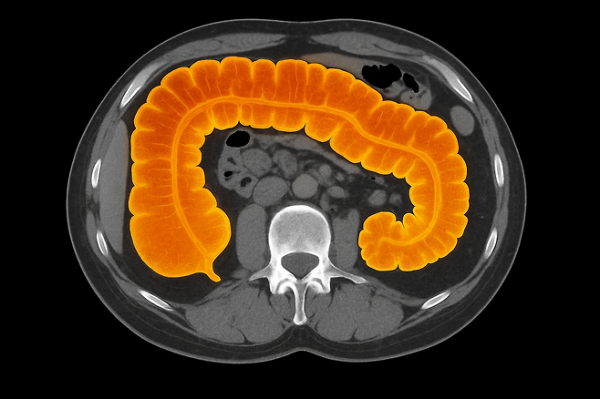

“대장암”이 시작되는 초기 증상 6가지

대장암은 초기에 특별한 통증이 없어 발견이 늦어지는 경우가 많습니다. 하지만 몸은 이미 작은 신호들을 보내고 있습니다. 오늘은 대장암이 시작될 때 나타나는 초기 증상 6가지를 알아보겠습니다.